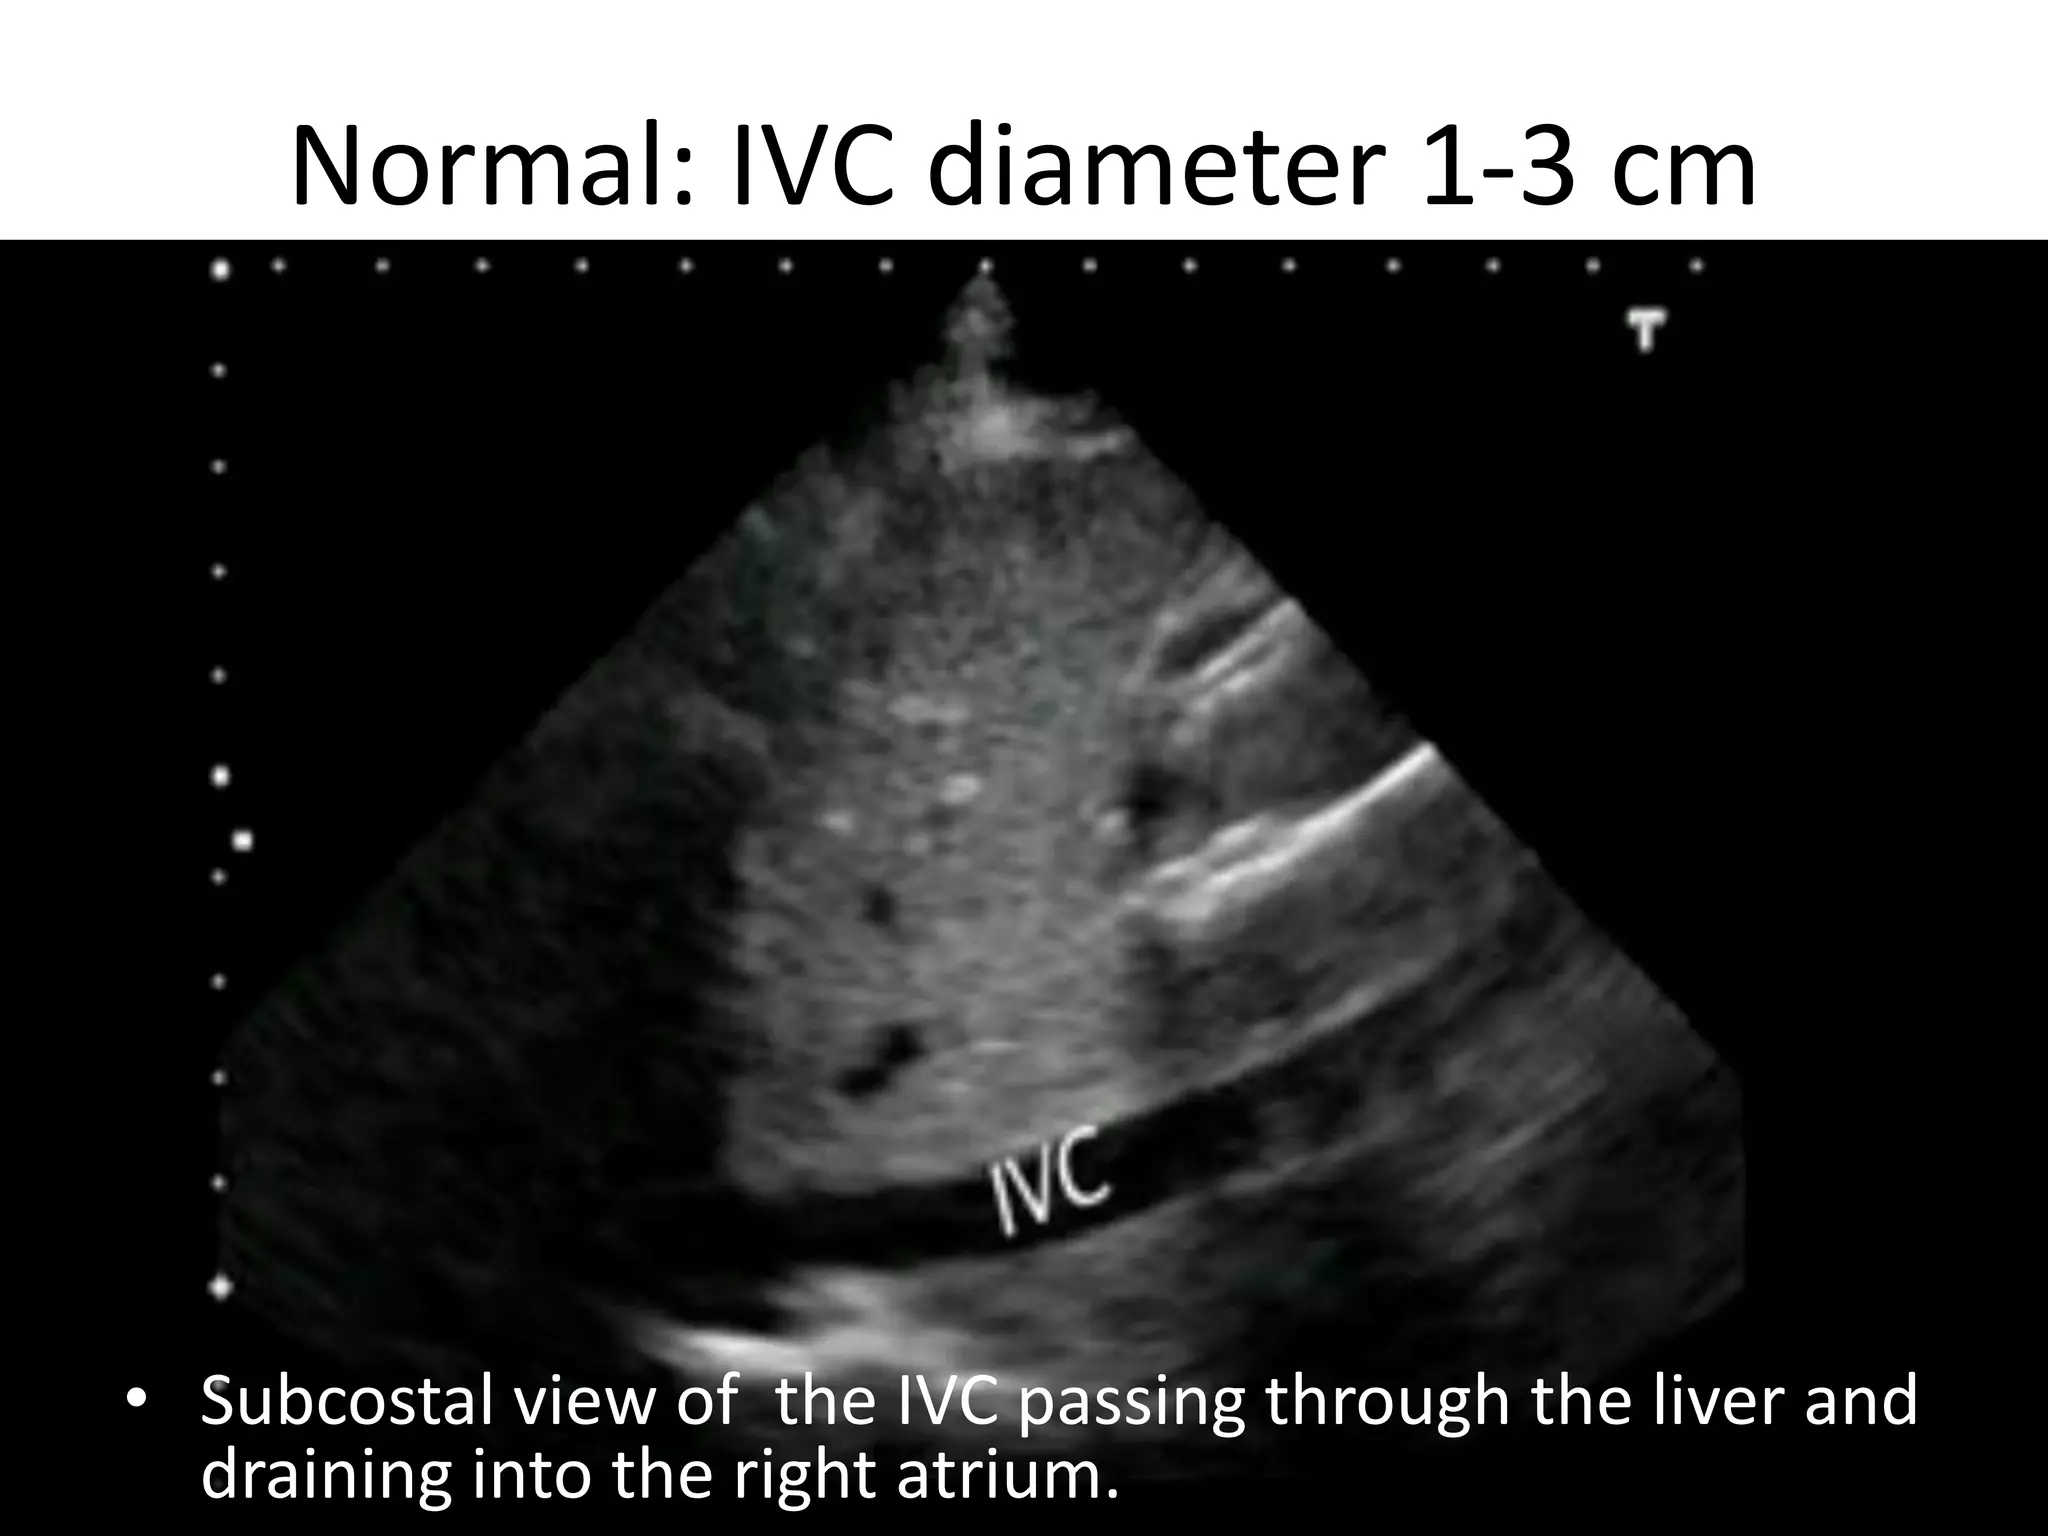

Normal: IVC diameter 1-3 cm

• Subcostal view of the IVC passing through the liver and

17

draining into the rightBassel Ericsoussi, MD

atrium.

Normal: IVC diameter1-3 cm • Subcostal view of the IVC passing through the liver and 17 draining into the rightBassel Ericsoussi, MD atrium.